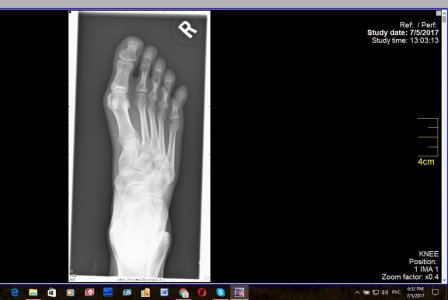

Здравствуйте! Прошу помощи. Прошло 18 дней со дня перелома мизинца (4 июля), к сожалению,находясь заграницей так и не удалось попасть к нормальному врачу, ходила с примотанным пластырем к соседнему пальцу, синяк почти прошел, сегодня сделали снимки - по -моему разницы никакой, угол отломка не изменился, при опоре на мизинец чувствуется давление и распирание внутри, будто эта кость торчит там внутри что-ли, как мешает что-то, при опоре отъезжает и смотрит немного в сторону, расстояние с соседним пальцем больше, чем на здоровой ноге. Думаю насчет возврата на родину и лечения в Москве. Вопрос - можно и нужно ли его еще как-то вправить, какой предельный срок? Не станет ли хуже от этих правок?

Забыть и ходить как есть? Какие последствия если не так срастется? Дискомфорт при ходьбе будет? Для меня это очень важно, заранее благодарю за ответ. Первый снимок - сразу после перелома 4 июля, остальные - 22 июля.